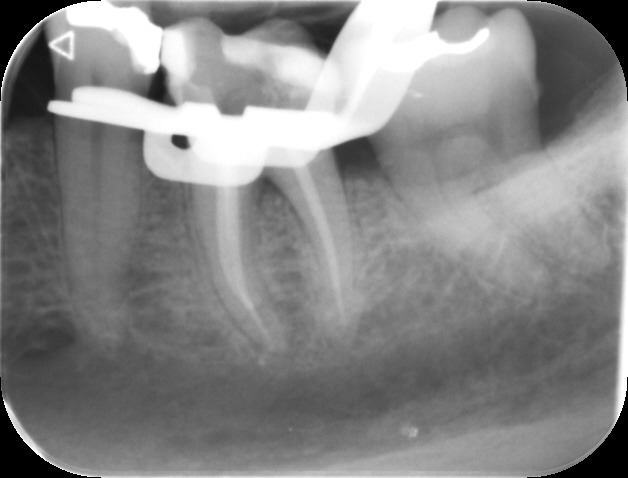

An access cavity is placed on the surface where the patient bites, to reach the root canals of the tooth. Once all the canals are identified, small files are used to remove the infected pulp.

Files of different sizes are used to eliminate bacteria and infection and to shape the canals. The canals are disinfected thoroughly with irrigants and later the canals will be sealed in 3 dimensions with a special medicament called gutta-percha to prevent reinfection of the tooth and the access cavity will be sealed with a temporary filling.